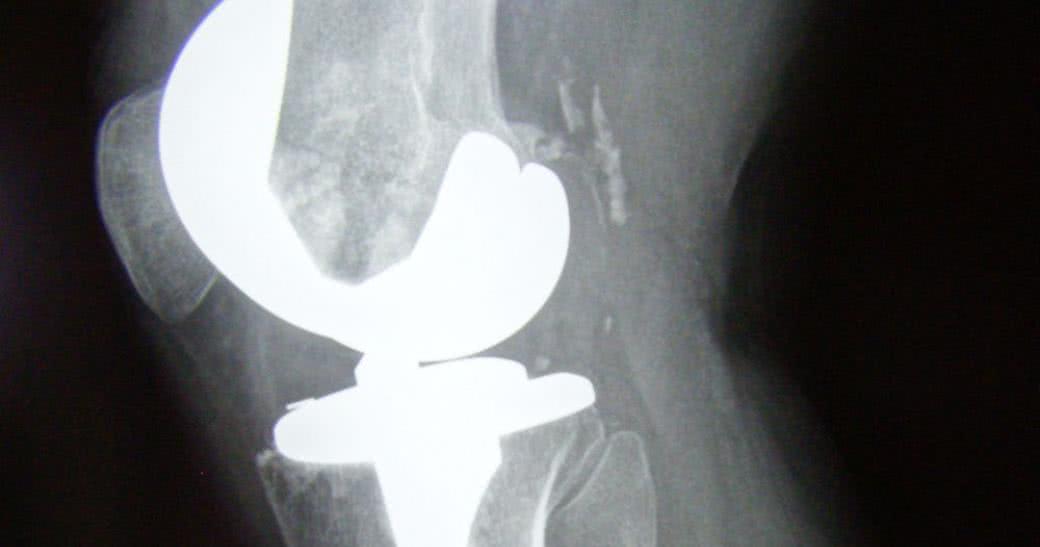

Podczas zabiegu chirurg usuwa uszkodzoną tkankę chrzęstną oraz niewielkie fragmenty kości tworzące staw. Następnie na ich miejsce wstawia sztuczny staw z metalu i polietylenu i mocuje go za pomocą kleju kostnego (tzw. cementu). Jeśli po operacji nie wystąpią komplikacje, pacjent spędza w szpitalu mniej więcej 5 dni, po czym przez miesiąc wraca do zdrowia w domowym zaciszu. Do normalnej aktywności powrócić może z kolei w ciągu 2-3 miesięcy.